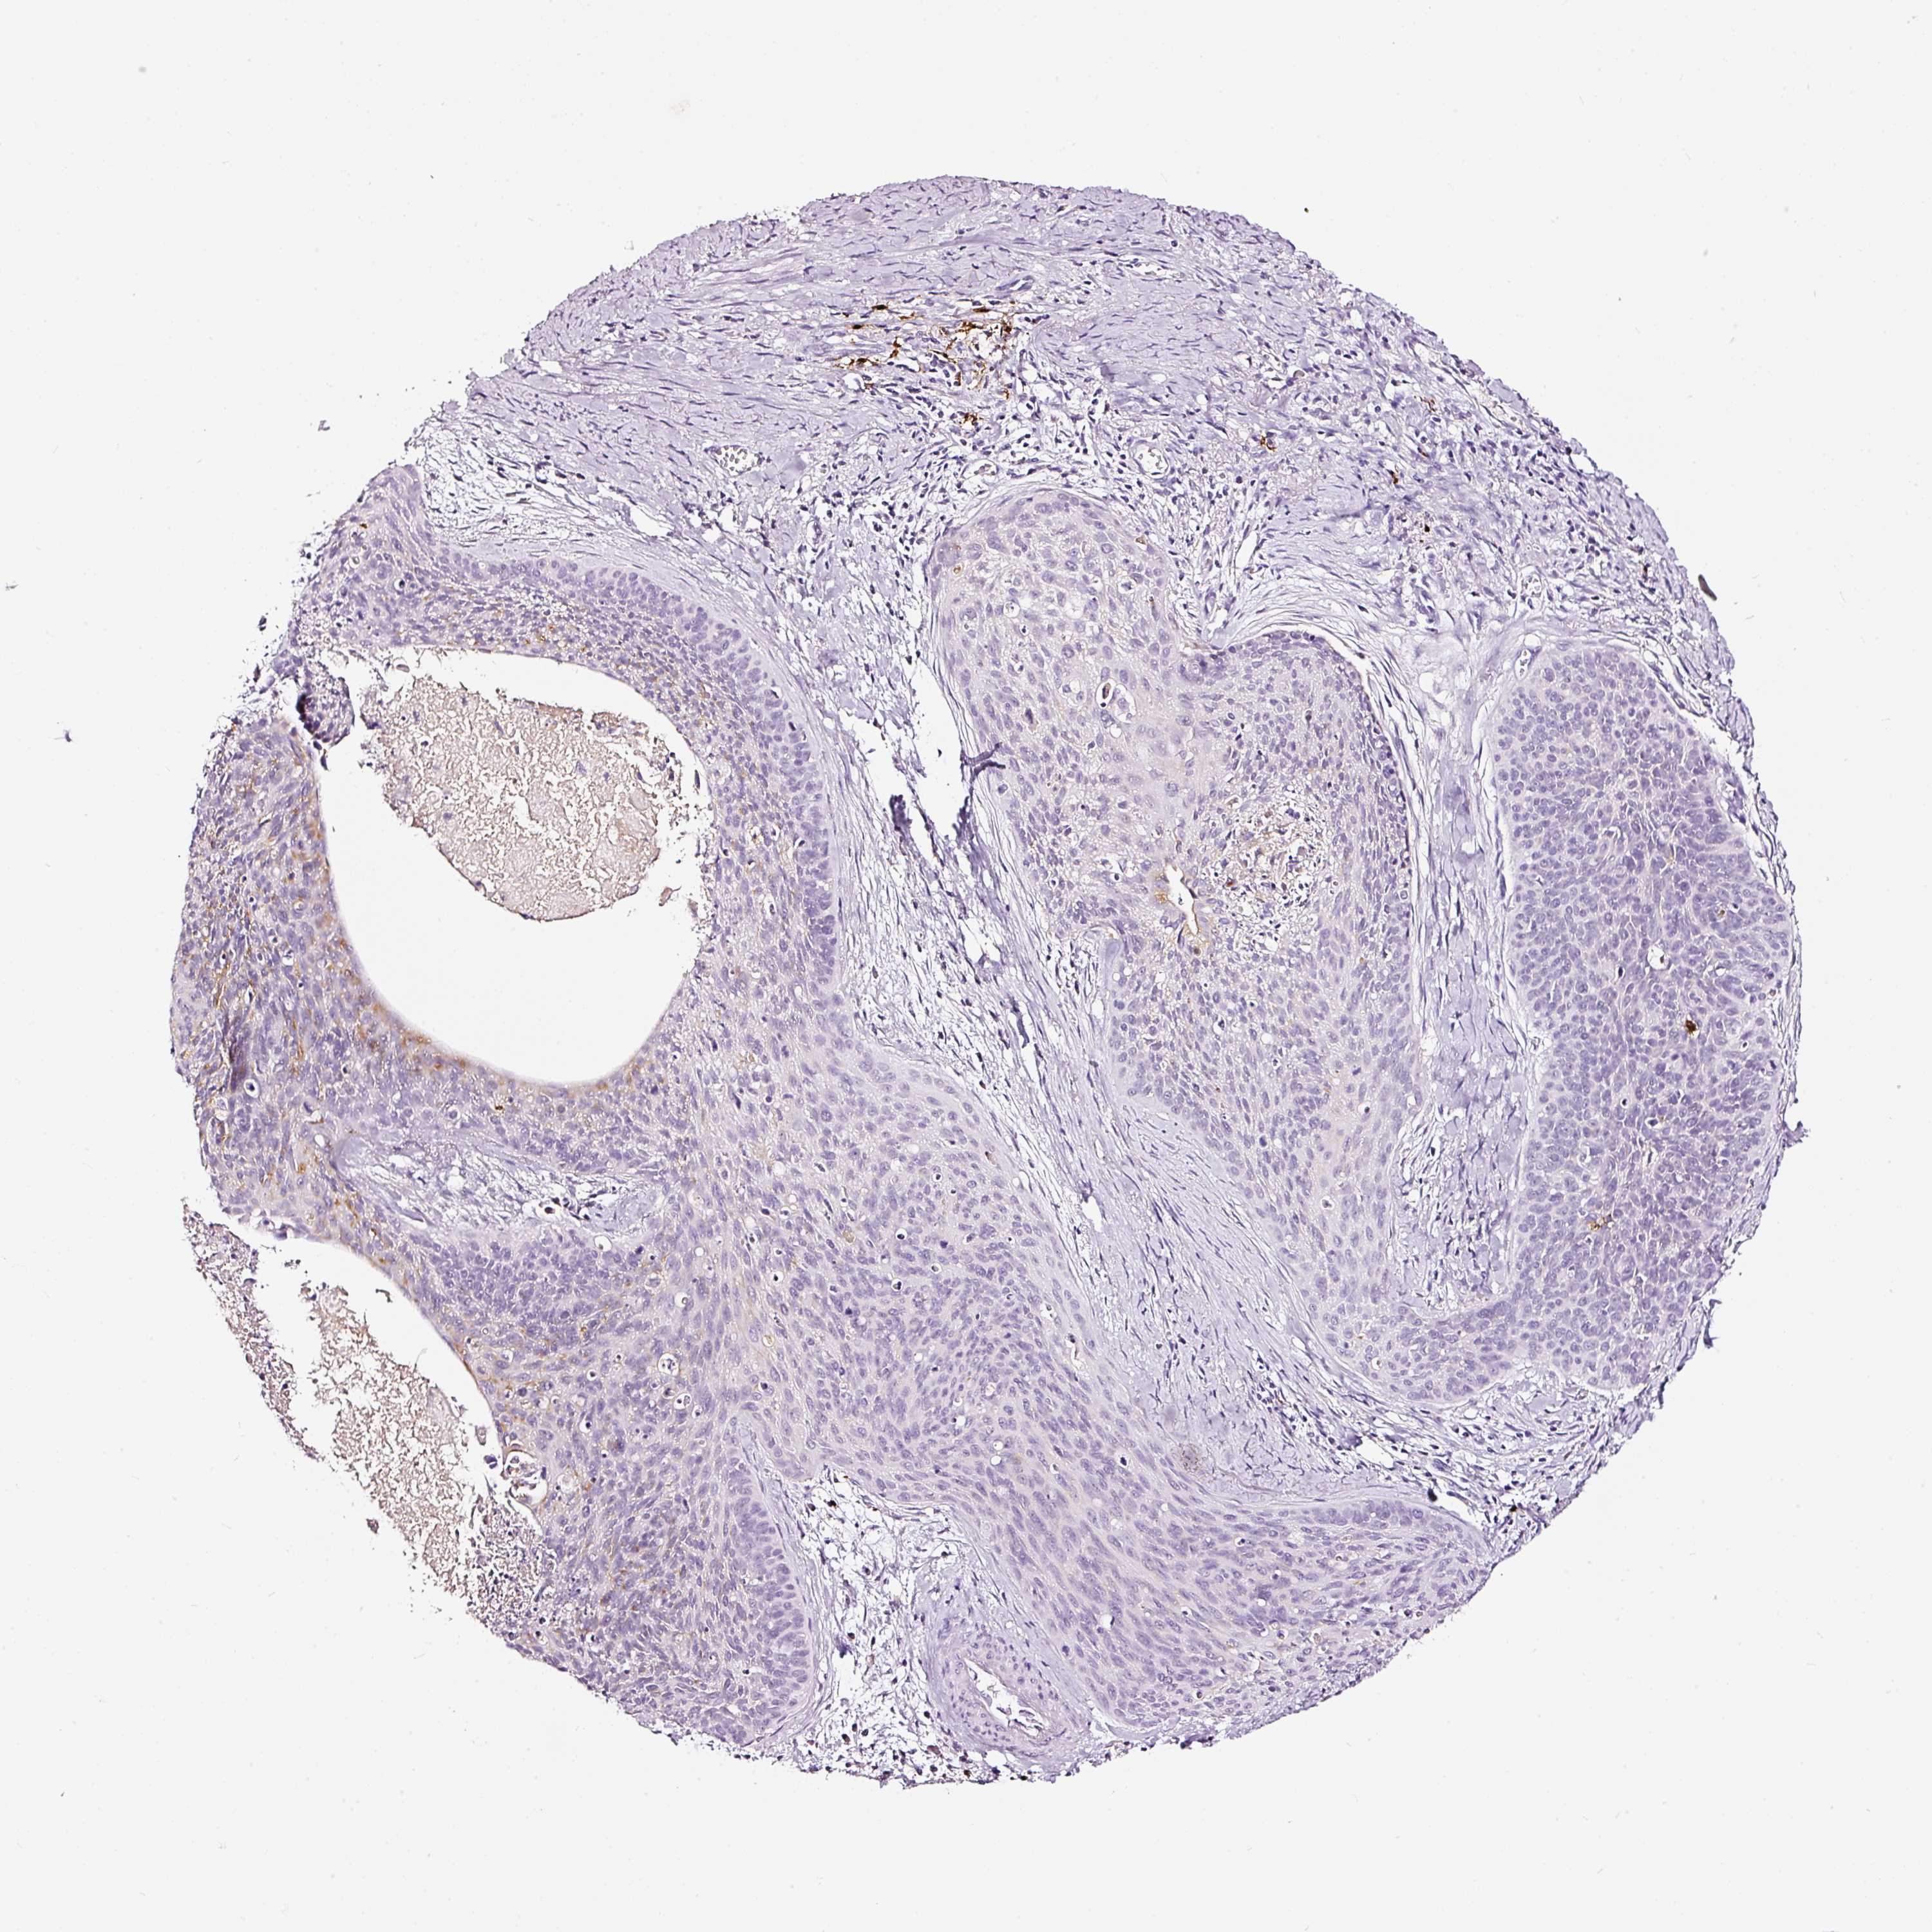

CERVICAL CANCER - Protein expressioni

A mouse-over function shows sample information and annotation data. Click on an image to view it in a full screen mode. Samples can be filtered based on level of antibody staining by selecting one or several of the following categories: high, medium, low and not detected. The assay and annotation is described here.

Note that samples used for immunohistochemistry by the Human Protein Atlas do not correspond to samples in the TCGA dataset.

Antibody stainingi

Antibody staining in the annotated cell types in the current human tissue is reported as not detected, low, medium, or high, based on conventional immunohistochemistry profiling in selected tissues. This score is based on the combination of the staining intensity and fraction of stained cells.

Each image is clickable and will lead to virtual microscopy that enables deeper exploration of all samples and also displays staining intensity scores, fraction scores and subcellular localization as well as patient and tissue information for each sample.

Antibody HPA051467

Antibody CAB025133

Squamous cell carcinoma, NOS

Adenocarcinoma, NOS